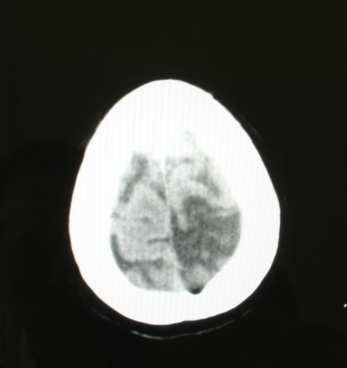

和外伤没有关系, 可以认为是陈旧病变。

除考虑脑软化,也不排除转移灶。

局部脑沟有变化,建议强化,不除外血管畸形或转移性病变.

位置表浅 ct值28-31 建议增强或mr检查